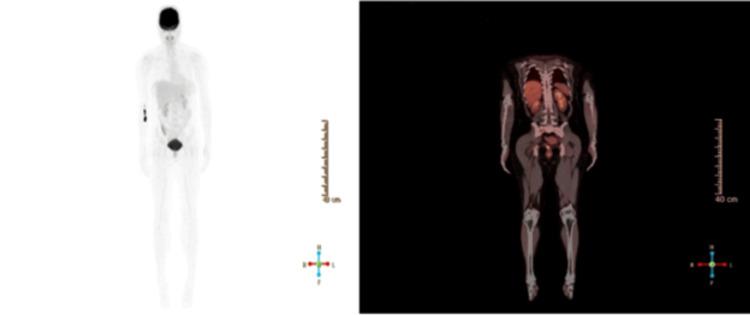

Amelanotic melanoma (AM) is a rare and aggressive subtype of cutaneous melanoma that lacks the characteristic pigmentation, which makes it challenging to diagnose, often resulting in delayed treatment. Nodular melanoma (NM), a subtype of AM, is associated with a poorer prognosis and is infrequently reported in the Middle East and North Africa (MENA) region. AM is a rare and aggressive subtype of cutaneous melanoma, accounting for approximately 1-8% of all melanoma cases. We present the case of a 39-year-old Filipino female with a slowly enlarging, skin-colored lesion on her right patella, initially misdiagnosed as a dermatofibroma. The lesion was later confirmed as type IIIb cutaneous amelanotic nodular melanoma via histopathology and immunohistochemistry, with a Breslow thickness of 5 mm and Clark level IV invasion. Sentinel lymph node biopsy revealed nodal involvement, and the patient underwent wide local excision followed by adjuvant immunotherapy. This report highlights the diagnostic challenges posed by AM, particularly in younger patients and in regions where such cases are rarely reported. Accurate diagnosis requires a high index of suspicion and a multimodal diagnostic approach. Early recognition and intervention are crucial for improving patient outcomes in this aggressive malignancy.

无色素性黑色素瘤(AM)是皮肤黑色素瘤中一种罕见且侵袭性强的亚型,缺乏典型色素沉着,这使其诊断具有挑战性,常导致治疗延迟。结节性黑色素瘤(NM)作为AM的一种亚型,预后较差,在中东和北非(MENA)地区鲜有报道。AM是皮肤黑色素瘤中一种罕见且侵袭性强的亚型,约占所有黑色素瘤病例的1 - 8%。我们报告一例39岁菲律宾女性病例,其右髌骨上有一缓慢增大的肤色病变,最初被误诊为皮肤纤维瘤。该病变后来经组织病理学和免疫组织化学确诊为IIIb型皮肤无色素性结节性黑色素瘤,Breslow厚度为5毫米,Clark分级为IV级浸润。前哨淋巴结活检显示有淋巴结受累,患者接受了广泛局部切除,随后进行辅助免疫治疗。本报告强调了AM带来的诊断挑战,尤其是在年轻患者以及此类病例鲜有报道的地区。准确诊断需要高度的怀疑指数和多模式诊断方法。早期识别和干预对于改善这种侵袭性恶性肿瘤患者的预后至关重要。